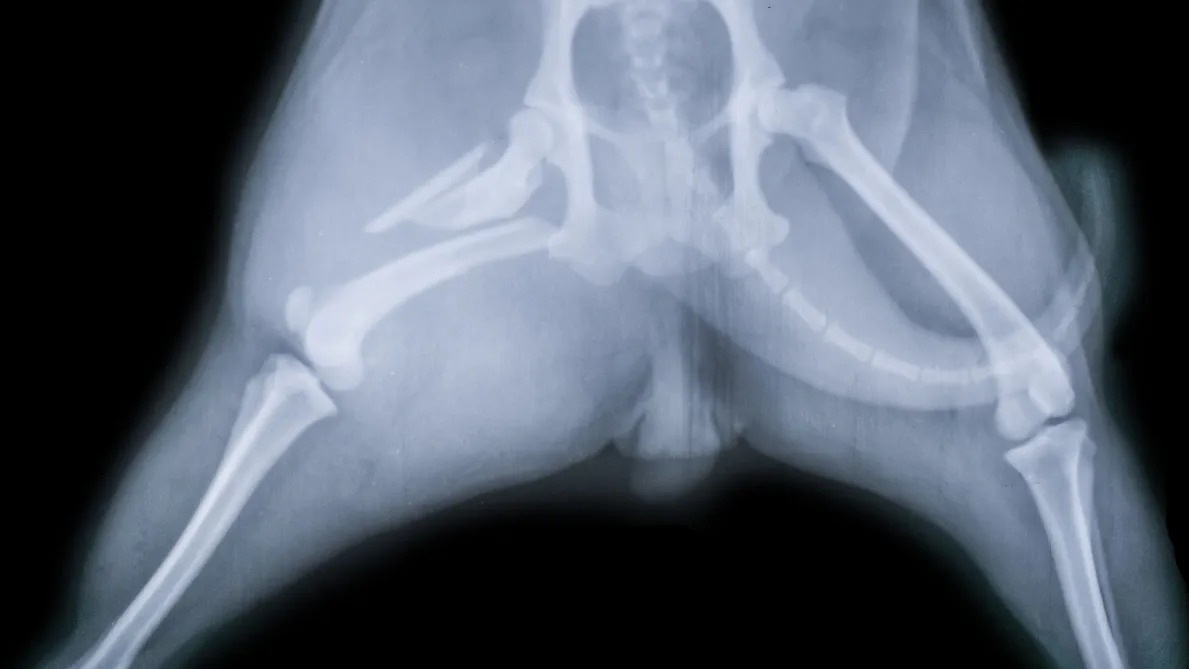

A pet X-ray, or radiograph, is a non-invasive diagnostic tool that uses radiation to create images of the inside of your pet's body. It allows us to visualize bones, organs, and soft tissues, helping us identify fractures, tumors, infections, or abnormalities that might not be visible through a physical exam alone. This tool is essential for a variety of reasons, from routine check-ups to emergency situations.

An X-ray is crucial for diagnosing conditions like broken bones, joint problems, and spinal issues. It is also helpful for detecting internal issues such as heart disease, lung problems, or digestive disorders. For pets that are showing signs of distress or unexplained pain, an X-ray can help our team pinpoint the problem and determine the best course of action for treatment. Using the latest technology and our expertise, we ensure a precise and efficient process that leads to quick results.